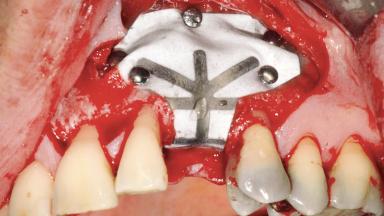

Bone Augmentation | Staged|Vertical |

Augmentation Materials | Autogenous chips|Membrane |